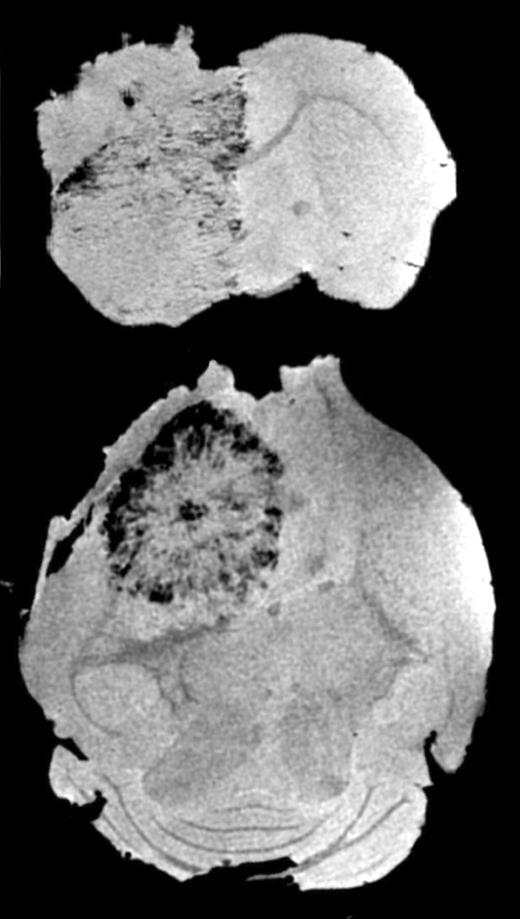

Serial MRI in mice that received magnetically labeled Sca1+ bone marrow cells, group 2. See the complete figure in the article beginning on page 420.

In this issue of Blood, Anderson and colleagues have used magnetic resonance imaging (MRI) to follow magnetically labeled transplanted cells. In the reported studies, Sca1+ endothelial progenitor cells were labeled with superparamagnetic iron oxide nanoparticles (SPIOs) and then injected into the vasculature of animals. In mice with orthotopically implanted gliomas, the labeled cells tracked to the tumor periphery and were initially visible by MRI as a slight darkening surrounding the tumor 9 days after implantation. At later time points, the darkening became more pronounced and progressed to a significant hypointense ring surrounding the tumor. Ex vivo high-resolution MRI (see figure) showed that labeled cells were also infiltrating into the interior of the tumors. In temporal studies, histology demonstrated that MR signals were present only when tumors were undergoing neovascular growth, and immunohisotchemistry confirmed that iron-containing cells within the tumor and its periphery were positive for 2 endothelial cell markers, CD-31 and von Willebrand factor. Although the study did not control for the potential leakage of iron from the transplanted cells and subsequent redistribution to vasculature, there are significant data from other studies to strongly suggest that this is not the mechanism in place.3 Furthermore, the use of labeled nonviable cells for control animals supports the authors' conclusions that ex vivo–labeled progenitor cells migrate and differentiate into endothelial cells and are responsible for the signal changes observed.